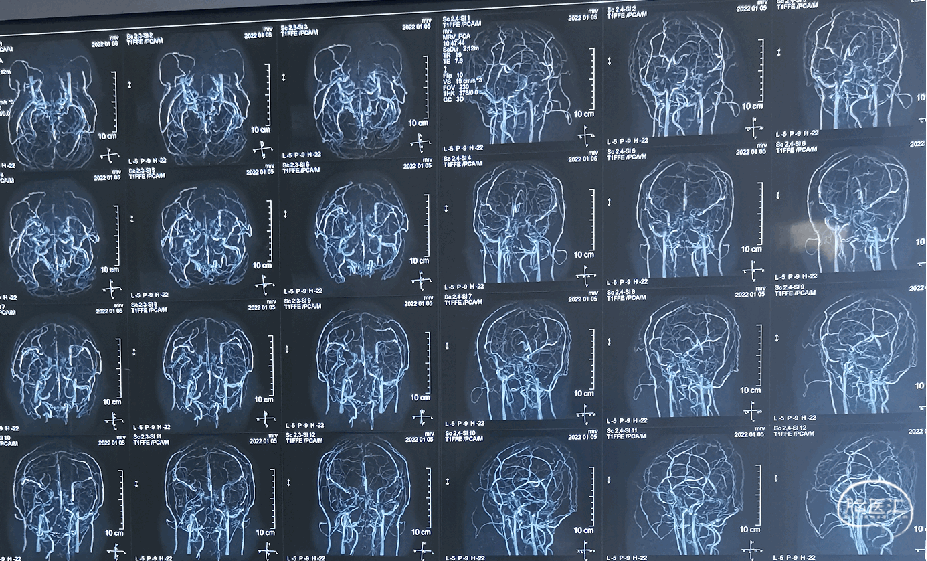

头颅MRV(2022-1-5)

头颅核磁:可见横窦高密度

影 像